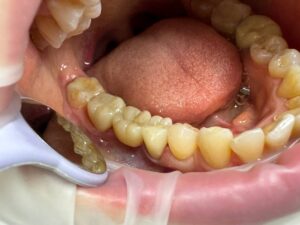

Зуб 36, керамическая коронка из диоксида циркона. Лучший выбор на жевательную группу зубов. Цена 22 000 рублей под ключ*